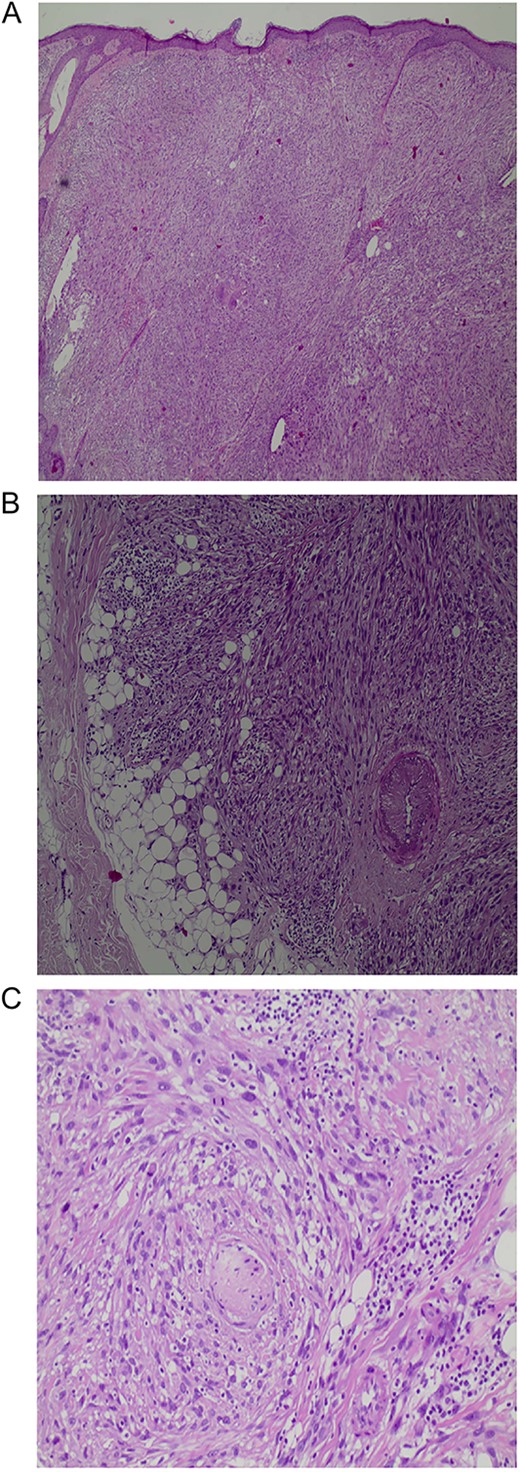

The histopathologic diagnosis was established based on the presence of irregular infiltrating spindle and pleomorphic tumor cells, which showed an invasive architectural pattern and extended to the subcutaneous tissue (Fig. 2A). The tumor consisted of large polyhedral to cuboid tumor cells with moderate to abundant eosinophilic and rarely clear cytoplasm. Furthermore, the tumor cells demonstrated marked nuclear pleomorphism and prominent nucleoli as well as many mitotic figures, including atypical forms. Other observed features included epidermal ulceration and perineural invasion (Fig. 2B and C).

A: An expansile tumor in the dermis (H&E, original magnification X40). B: Involvement of subcutaneous fat (H&E, original magnification X100). C: Perineural invasion (H&E, original magnification X200).